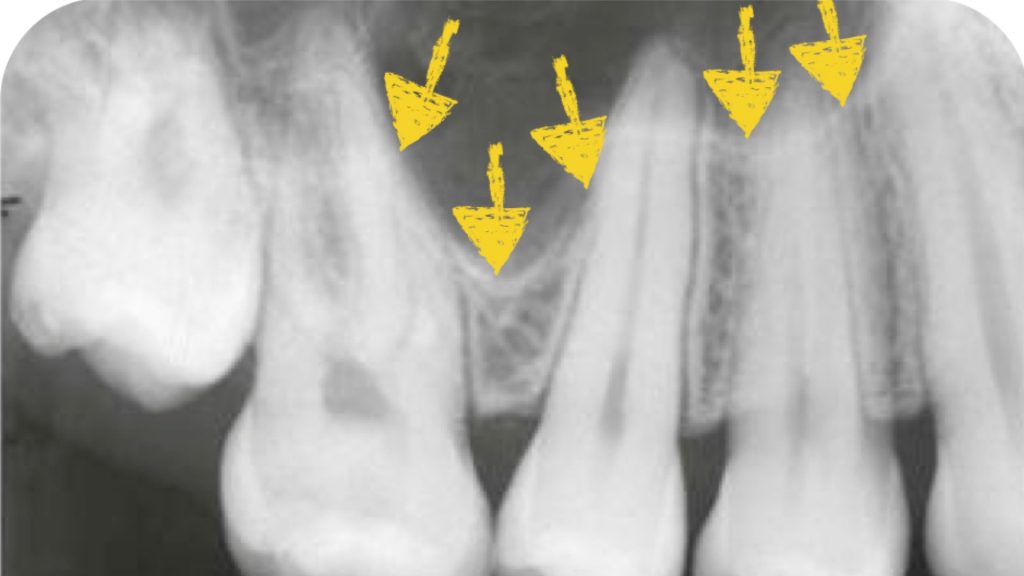

Exposure of Impacted Canine and Extraction of Adjacent Impacted Lateral Incisor

In this video, Dr. H. Ryan Kazemi presents a patient with delayed eruption of upper canine and lateral incisor and demonstrates the exposure and extraction technique.